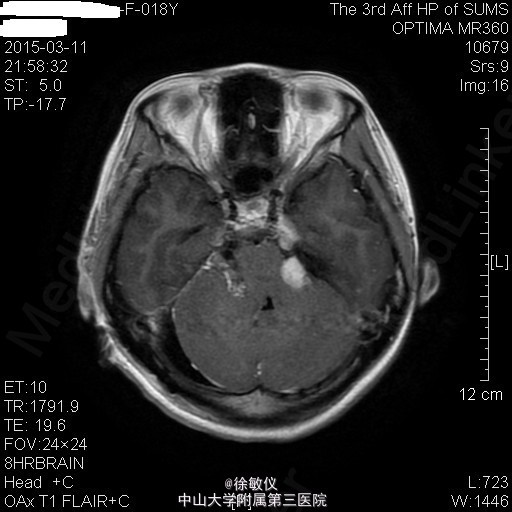

青年女性,主诉:左侧面部麻木,右侧听力下降半年。

查体:神清,查体合作,对答切题。颈软,无抵抗。左侧面部浅感觉痛觉过敏。双侧眼球运动正常,双侧视野粗测无缺损。右侧听力粗测听力下降。双侧瞳孔等大等圆,直径3mm,对光反射灵敏。双侧肢体肌力5级,肌张力正常。病理征未引出。 辅查:头颅MR提示:双侧桥小脑角区、鞍上池右侧、左侧三叉神经颅内段及枕部多发占位,考虑为神经纤维瘤病II型。

诊断:双侧听神经鞘瘤 排除手术禁忌症后,在全麻下行显微镜下经右侧乙状窦后入路右侧桥小脑角区占位病变切除术,术程顺利。术后于SICU监护治疗1天后顺利转回我科,予抗感染、脱水降颅压、营养支持及对症治疗,患者恢复良好。 术后病理诊断:(桥小脑角占位)形态结合免疫组化结果,符合神经鞘瘤。免疫组化结果(⑥):S100(+),Vim(+),Ki-67(1%+)。 术后复查头颅MR示:1、右侧听神经瘤术后改变,右侧桥小脑角区占位大部分已切除,术区少量积液同前;左侧侧脑室内少量积血,基本同前。 2、左侧桥小脑角区、鞍上池右侧、左侧三叉神经颅内段及枕部多发占位同前,考虑神经纤维瘤病。